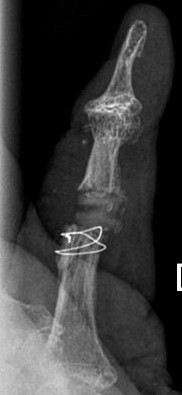

Die Röntgenbilder zeigen die implantierte Prothese im Zeigefingermittelgelenk bei gleichzeitiger Versteifung des Endgelenkes mit Schraube.

Blickfang ist hier das x-förmige Implantat zur Versteifung eines schmerzhaften und ehemals deformierten Endgelenkes.

Im Mittelgelenk fällt ein flauer "Schatten" von einem Kunstgelenk aus Silikon (Silikonendoprothese) auf.